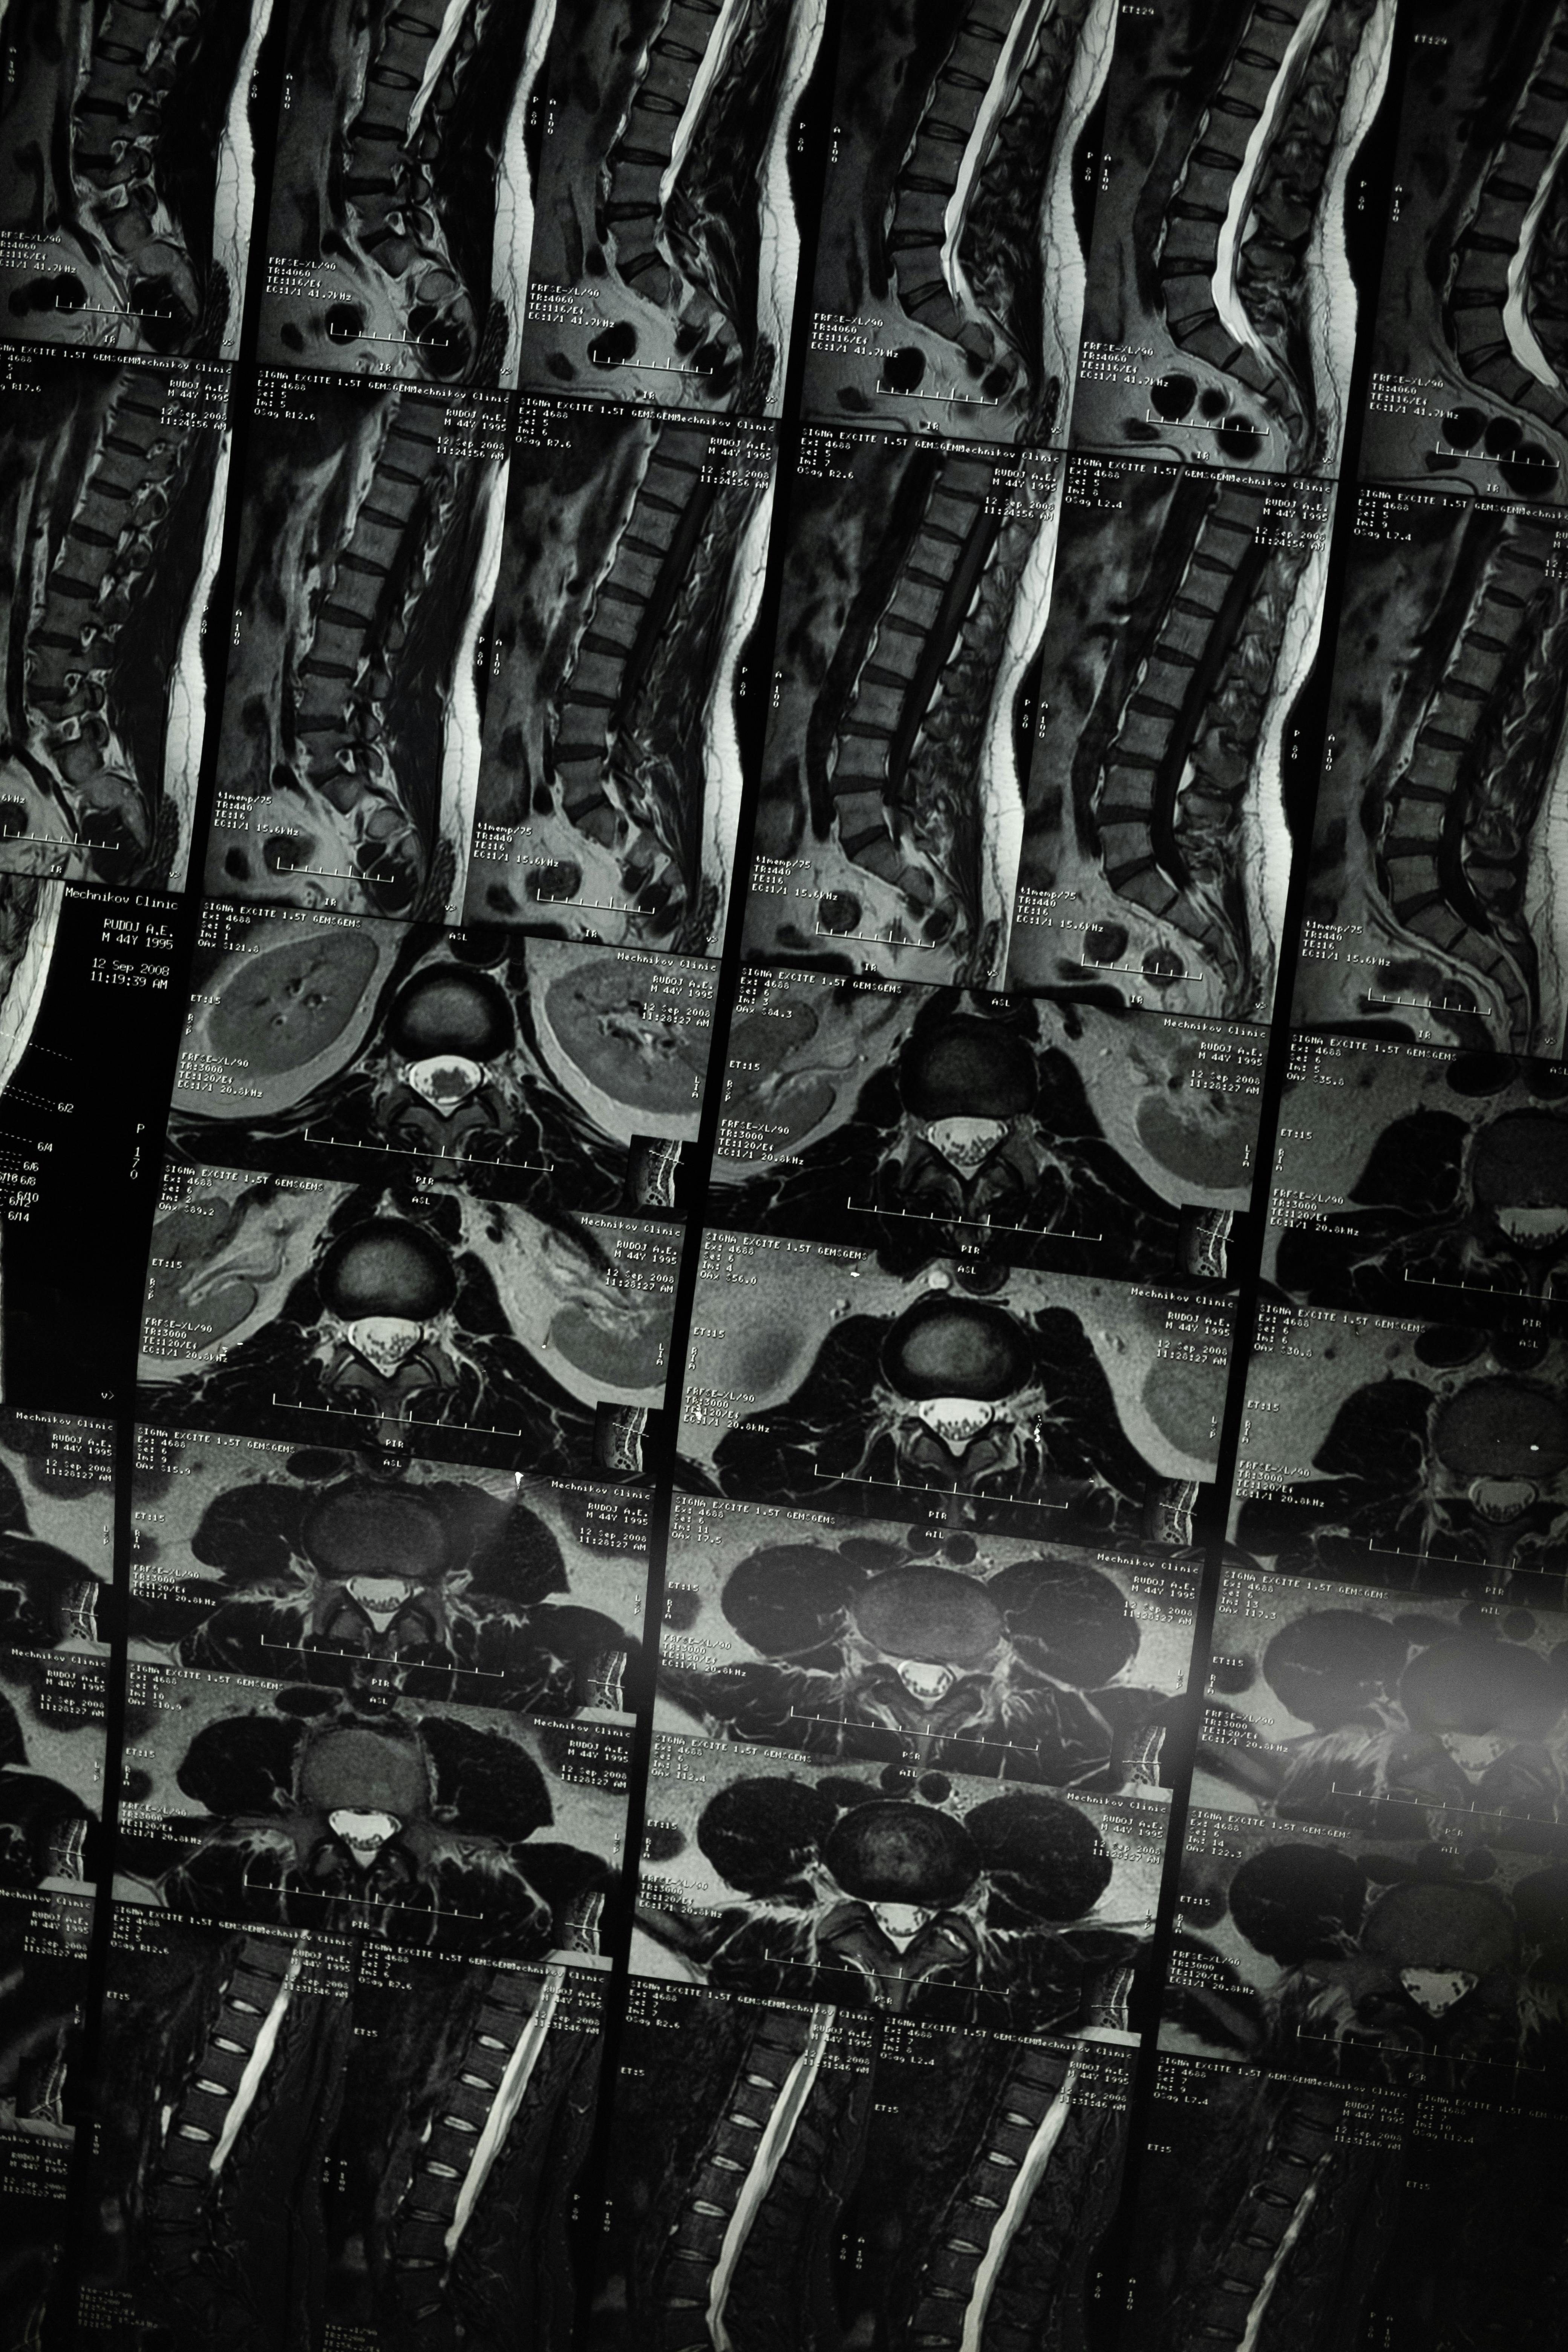

척추측만증은 척추가 정상적인 위치에서 옆으로 휘어지는 상태를 말합니다. 이 상태는 종종 청소년기에 발견되며, 경미한 경우가 많지만 심한 경우에는 통증이나 호흡 문제를 유발할 수 있습니다.

척추측만증의 원인

척추측만증의 원인은 다양하며, 대부분의 경우 명확한 원인을 알 수 없습니다. 이를 특발성 척추측만증이라고 하며, 가장 흔한 형태입니다. 그러나 일부 척추측만증은 특정 요인이나 상태와 관련이 있을 수 있으며, 이를 구조적 척추측만증과 비구조적 척추측만증으로 나눌 수 있습니다. 각각의 원인을 아래에 자세히 설명하겠습니다.